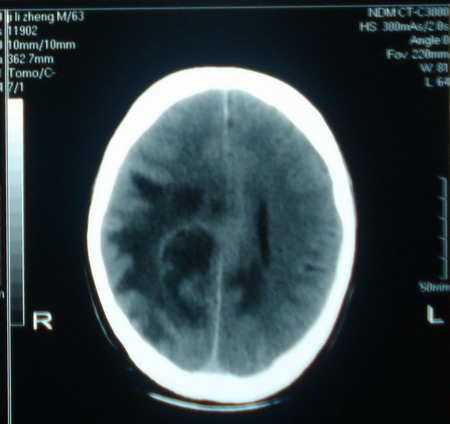

标题: CT13794:M63Y,头颅CT平扫 [打印本页]

标题: CT13794:M63Y,头颅CT平扫

男,63岁,头痛,呕吐,意识模糊一周。无发烧及感染史。

小肿瘤大水肿,考虑转移瘤

脑肿瘤 1 室管膜瘤 2 转移瘤

支持右侧丘脑恶性胶质母细胞瘤可能性大,建议增强进一步检查。